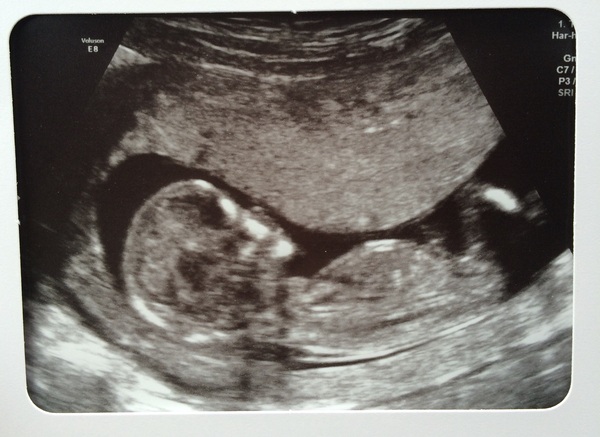

Here is my little baby, I'm convinced it's another boy! Nub theory guesses fully welcomed!